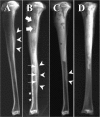

The therapeutic efficacy of an antimicrobial peptide, human lactoferrin 1-11 (hLF1-11), was investigated in a model of chronic methicillin-resistant Staphylococcus aureus (MRSA) (gentamicin susceptible) osteomyelitis in rabbits. We incorporated 50 mg hLF1-11/g or 50 mg gentamicin/g cement powder into a calcium phosphate bone cement (Ca-P) and injected it into the debrided tibial cavity, creating a local drug delivery system. The efficacy of hLF1-11 and gentamicin was compared to that of a sham-treated control (plain bone cement) (n=6) and no treatment (infected only) (n=5). The results were evaluated by microbiology, radiology, and histology. MRSA was recovered from all tibias in both control groups (n=11). On the other hand, hLF1-11 and gentamicin significantly reduced the bacterial load. Furthermore, no growth of bacteria was detected in five out of eight and six out of eight specimens of the hLF1-11- and gentamicin-treated groups, respectively. These results were confirmed by a significant reduction of the histological disease severity score by hLF1-11 and gentamicin compared to both control groups. The hLF1-11-treated group also had a significantly lower radiological score compared to the gentamicin-treated group. This study demonstrates the efficacy of hLF1-11 incorporated into Ca-P bone cement as a possible therapeutic strategy for the treatment of osteomyelitis, showing efficacy comparable to that of gentamicin. Therefore, the results of this study warrant further preclinical investigations into the possibilities of using hLF1-11 for the treatment of osteomyelitis.